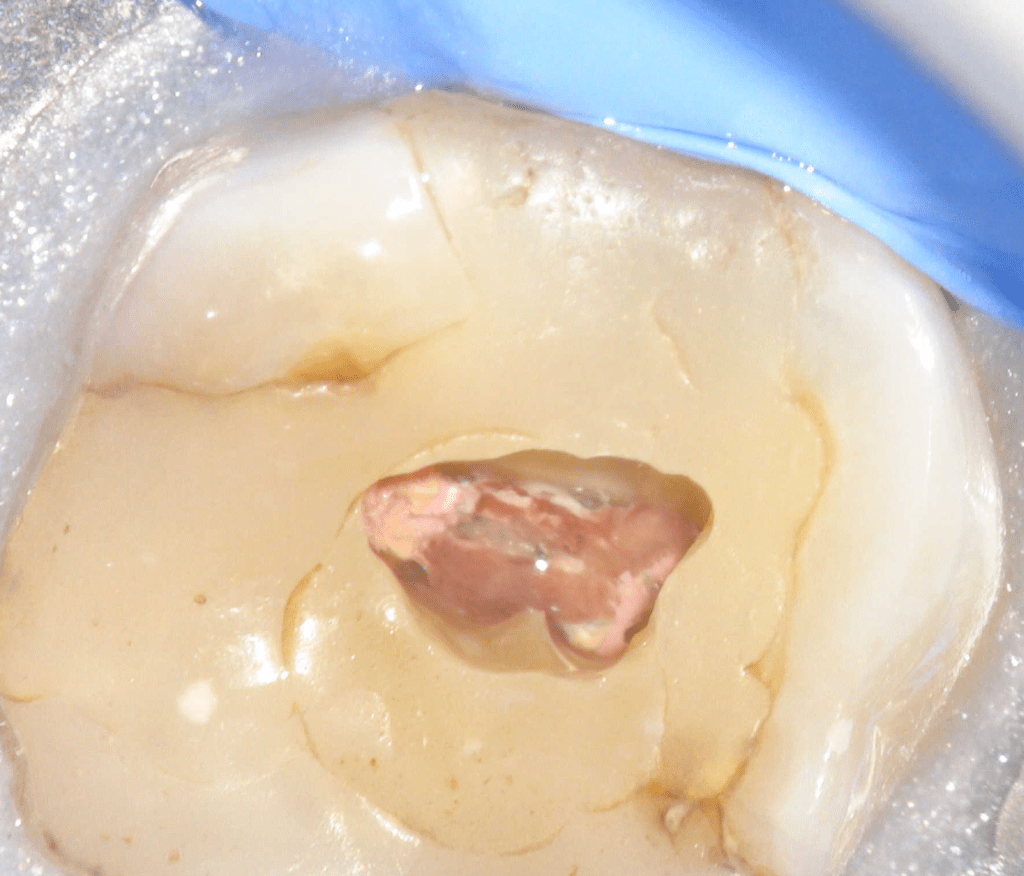

Fisura, remoción amalgama para explorar